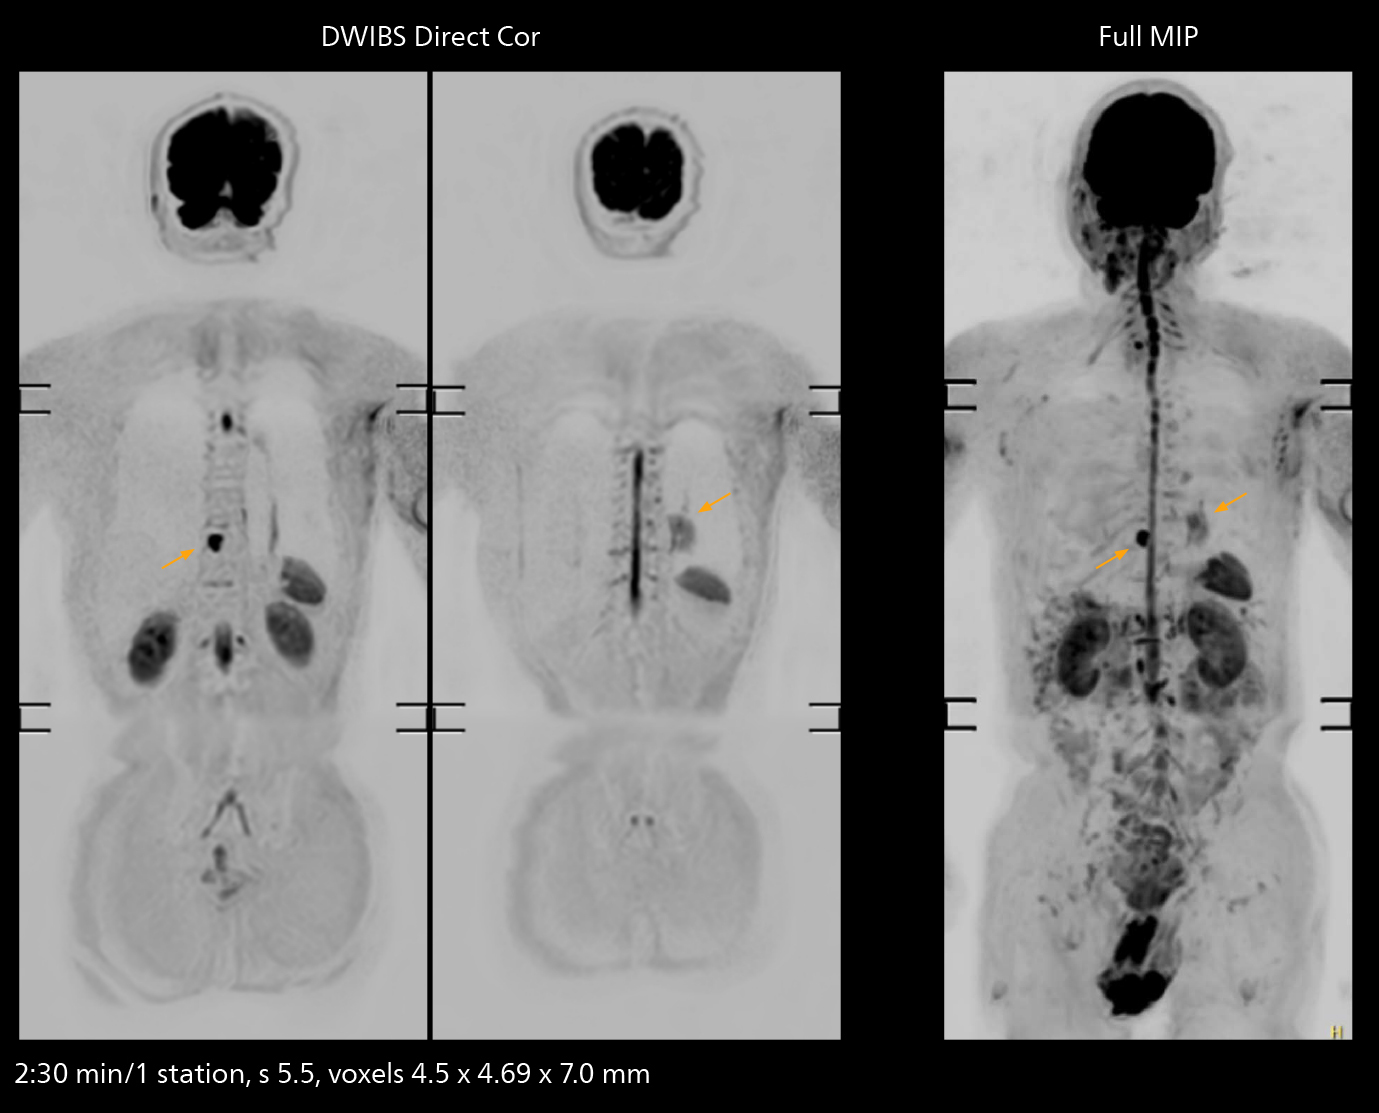

The value of the Elition X gradients is also evident in DWIBS studies. “The fact that we can consistently obtain distortion‐free DWIBS while reducing imaging time at three coronal stations is excellent,” Dr. Makuuchi says. “In these patients, it’s also important that the application of Compressed SENSE to T2‐weighted, STIR and mDIXON sequences has no impact on the examination time of whole‐body imaging. As a result of the increased speed and higher image quality we realize, DWIBS studies have now become routine examinations.”

Fast whole body DWIBS examination

With SmartPath to Elition X the team can obtain excellent quality DWIBS imaging and reduce imaging time. Other sequences also fit in the examination slot. This case shows left paravertebral neurogenic tumor and Th10 vertebral hemangiomas.

Fast whole body DWIBS examination

With SmartPath to Elition X the team can obtain excellent quality DWIBS imaging and reduce imaging time. Other sequences also fit in the examination slot. This case shows left paravertebral neurogenic tumor and Th10 vertebral hemangiomas.